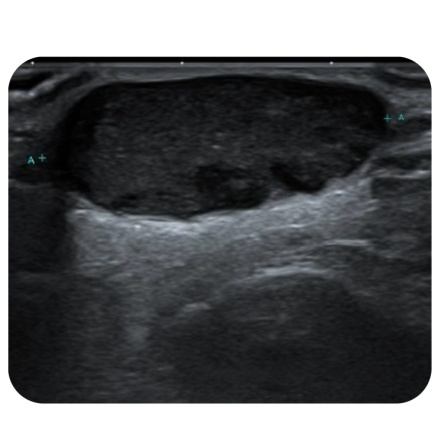

1.医生通过触诊及B超检查进行初步诊断。B超检查主要了解肿瘤的大小、性质、位置及血流情况。(*钙化上皮瘤有特征性表现:内部可见钙化灶;图左-表皮囊肿申宝配资,图右-钙化上皮瘤 )

图左-表皮囊肿

图右-钙化上皮瘤